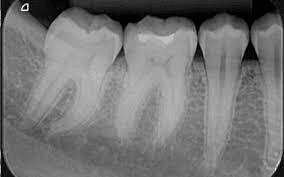

Bitewing radiographs

Bitewing radiographs show details of the crown to the level of supporting structures like the bone of both upper and lower jaws. Bitewing x-rays detect a cavity in between the teeth and are also used to check for any wear or broken dental restorations.